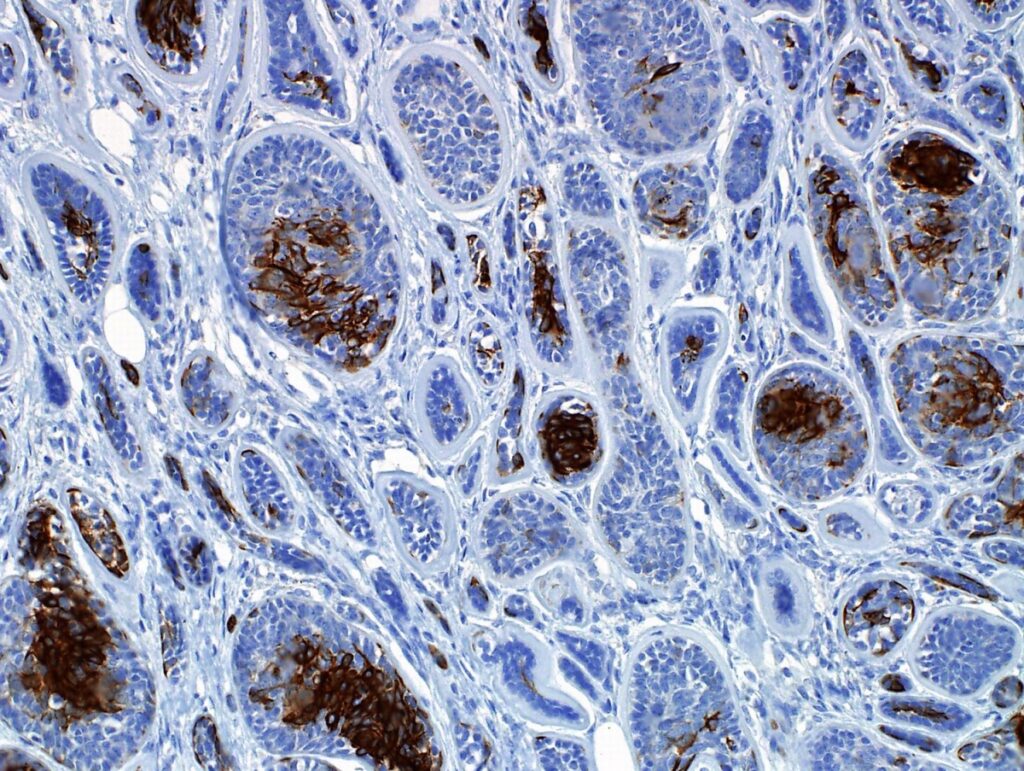

Pathology and molecular biology both make extensive use of the method of immunohistochemistry to reveal important details about cellular makeup, operations, and pathological states. So, immunohistochemistry is widely used in biomedical research in several fields, including cancer research, medication development, and diagnostic pathology.